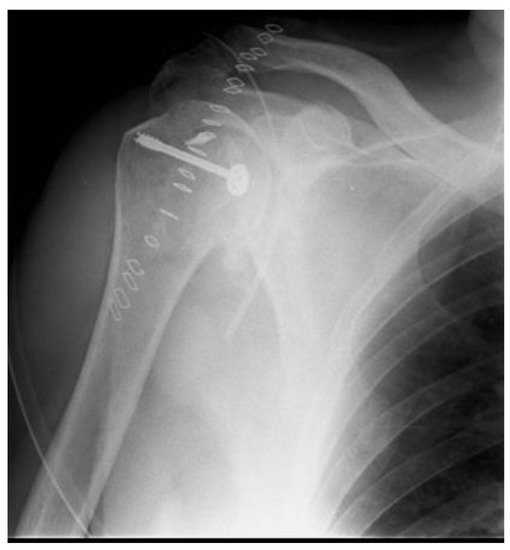

Posterior Shoulder Dislocation with Engaging Reverse Hill–Sachs Lesion: A Retrospective Study of Ten Patients Treated with Arthroscopy or Open Reduction and Stabilization

2. Materials and Methods

3. Results